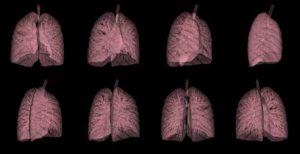

Immune Responses Underlying COPD Pathology

Chronic obstructive pulmonary disease (COPD) describes a largely untreatable and common set of lung pathologies affecting more than 80 million...